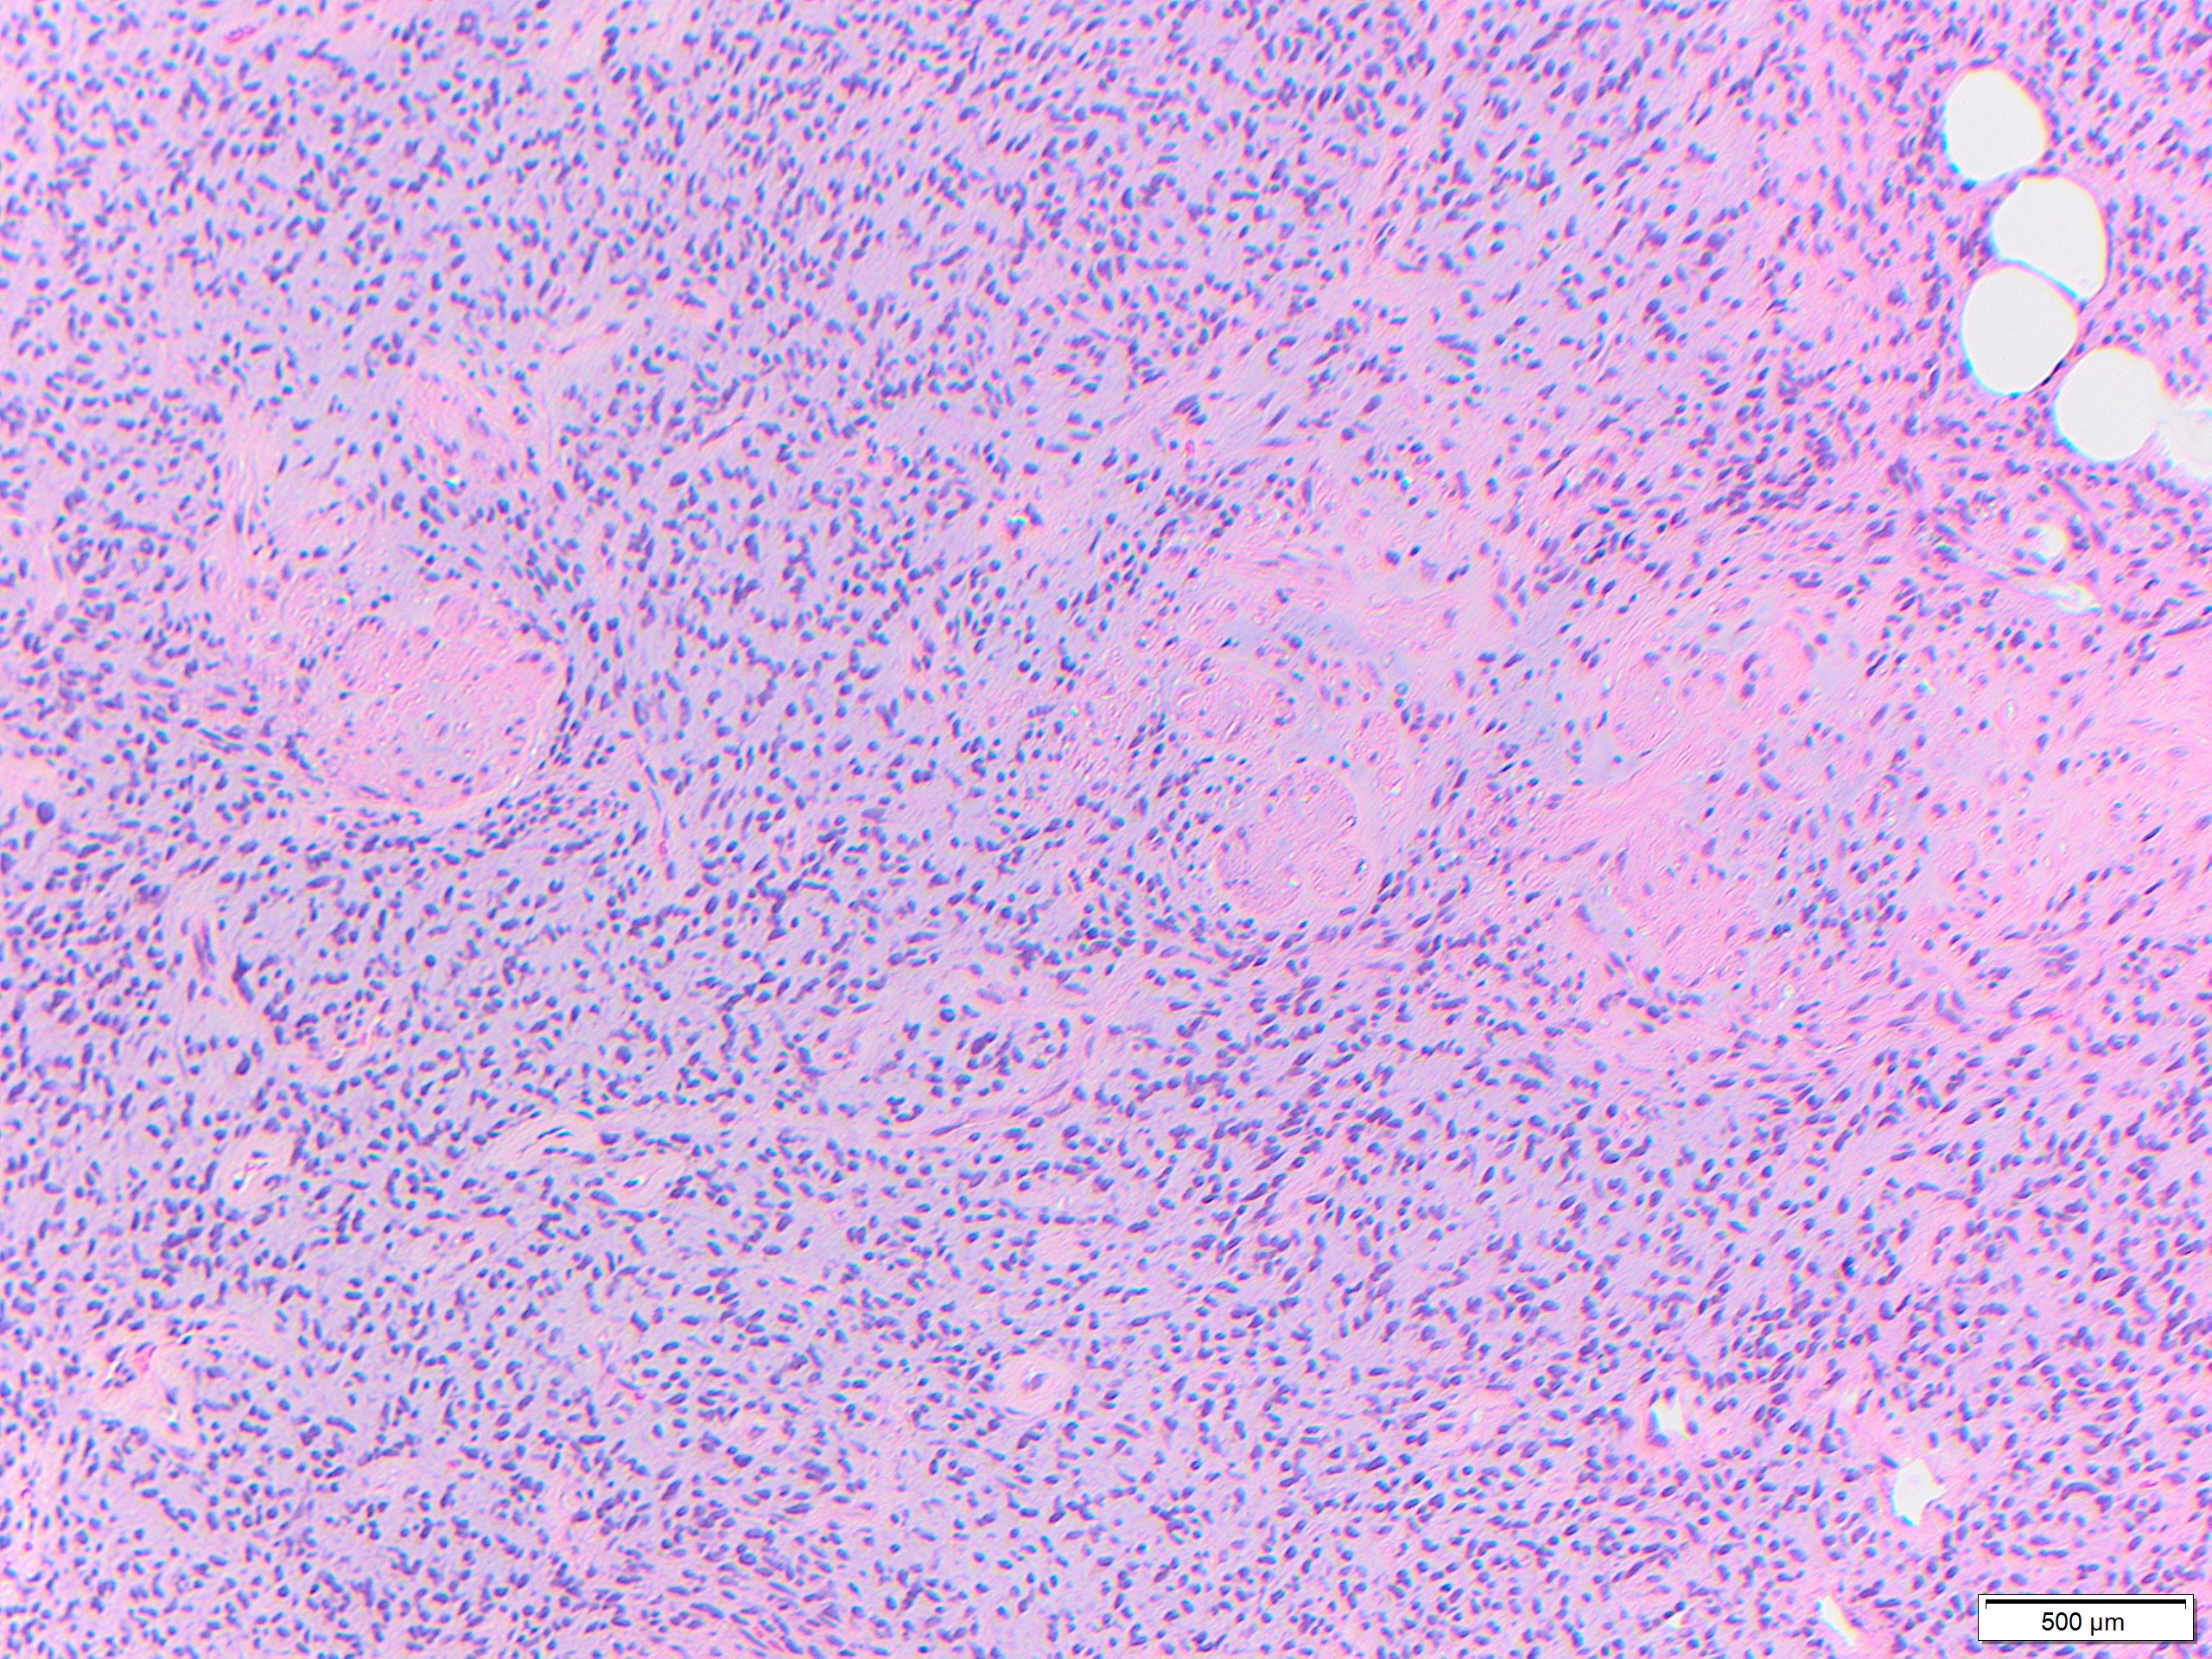

While these tumors may appear grossly circumscribed, microscopically DFSP are ill-defined with diffuse infiltration of dermis and subcutis. The tumor is composed of uniform spindled cells with collagenous stroma, often arranged in a storiform or “cartwheel” pattern, with infiltration of fat lobules and adnexal structures at the periphery. Some DFSP lack the collagenous storiform arrangement and instead display variably myxoid stroma, and some DFSP, like this example, may display myoid differentiation and so called “myoid-bodies” which may also be seen in other types of mesenchymal tumors. By immunohistochemistry DFSP are diffusely positive for CD34, and negative for S100, smooth muscle actin (SMA) and desmin, except myoid areas when present, are positive for SMA. Areas with herringbone architecture and loss of CD34 staining, may indicate fibrosarcomatous transformation. The histologic differential diagnosis of DFSP includes benign fibrous histiocytoma, neurofibroma, plaque-like CD34-positive dermal fibroma, and superficial acral fibromyxoma.